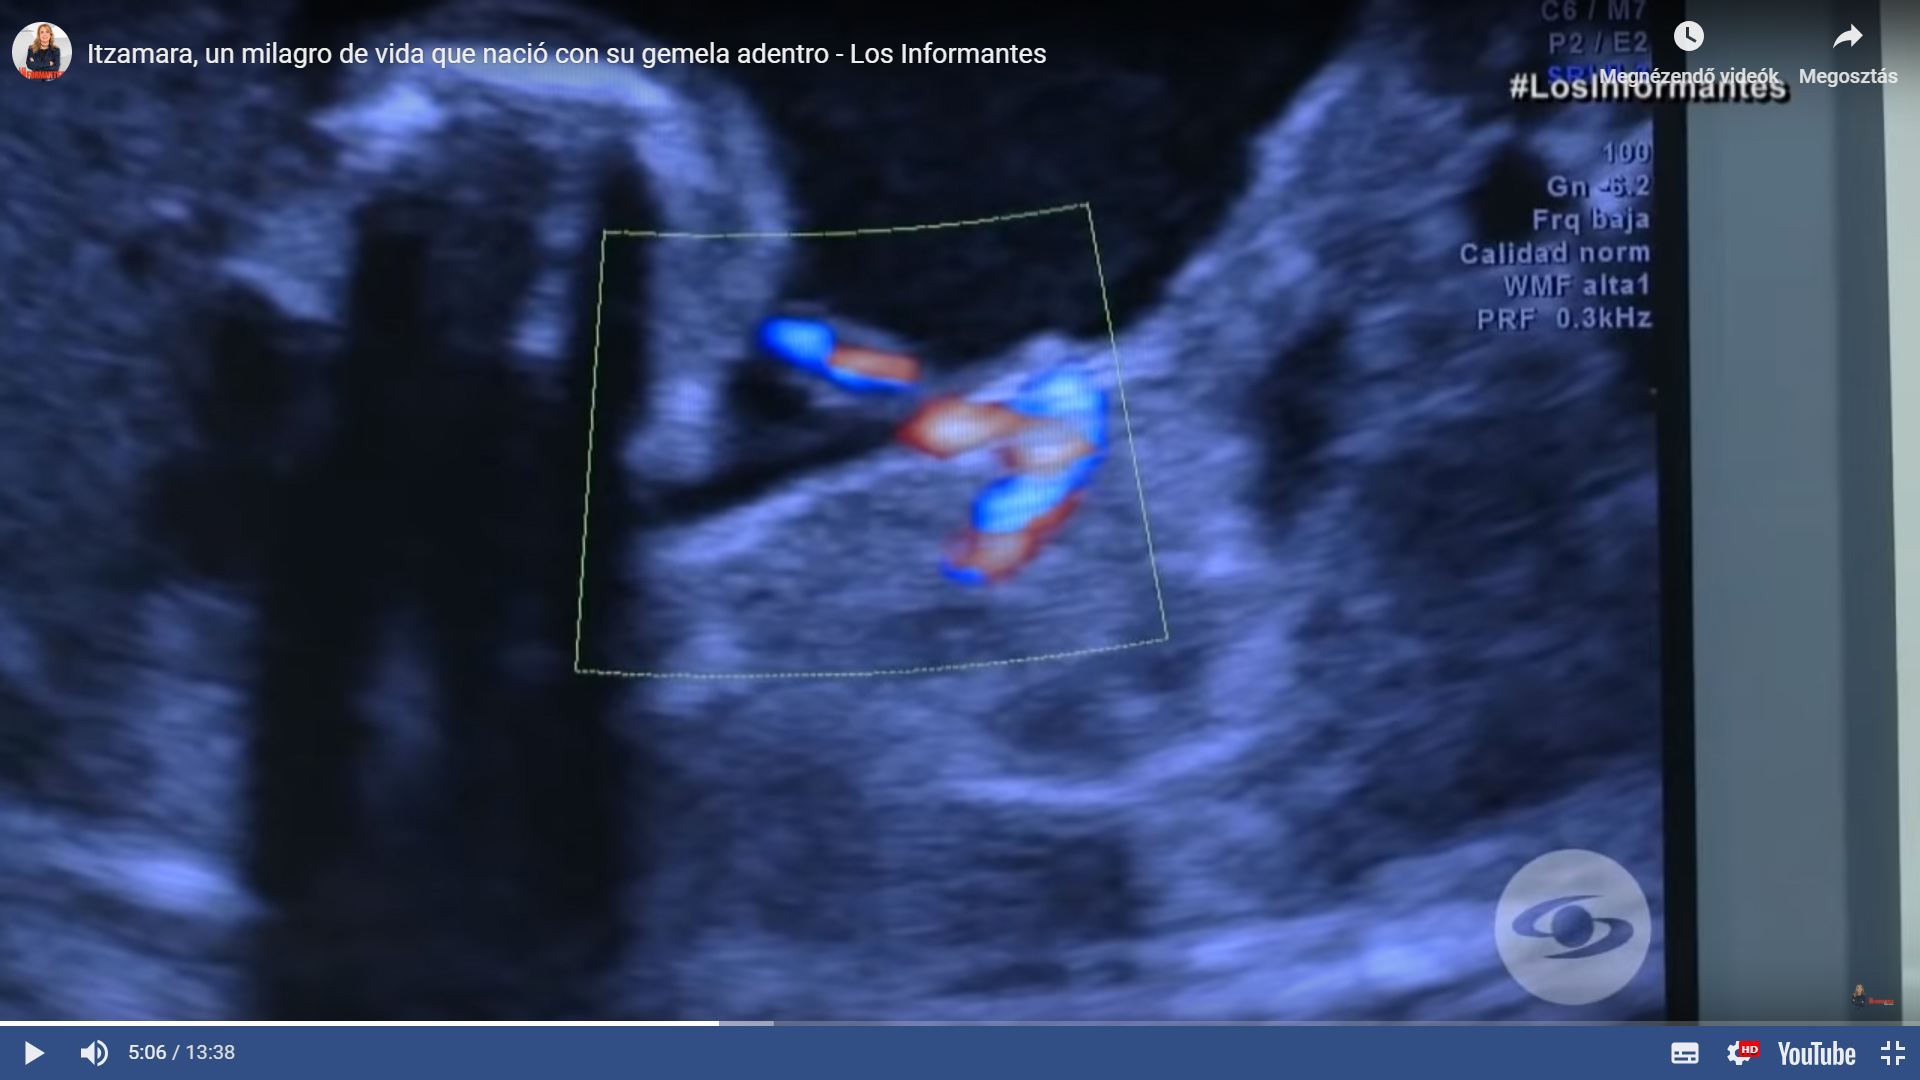

A különös terhességre a kismama nőgyógyásza, Dr Miguel Parra-Saavedra figyelt fel, aki a 35. heti 3D/4D ultrahangon észrevette, hogy valami nagyon nem stimmel a magzattal.